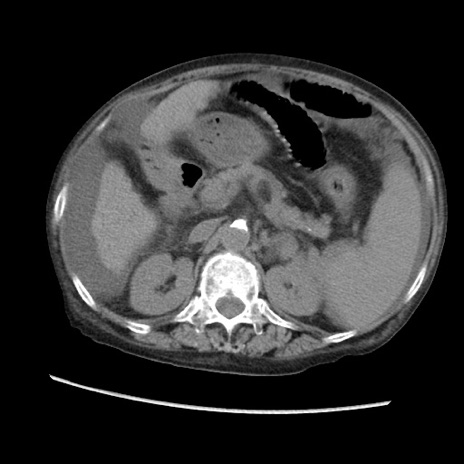

症例31(横断像)

【症例】80歳代 女性

【主訴】腹部膨満感

【現病歴】他院にて肝硬変にてフォロー中。1週間前から便秘、腹部膨満感、臍部腫瘤あり受診となる。

【既往歴】肝硬変

【身体所見】腹部膨隆あり、皮膚変化なし、疼痛なし。

【データ】WBC 4600、CRP 0.25